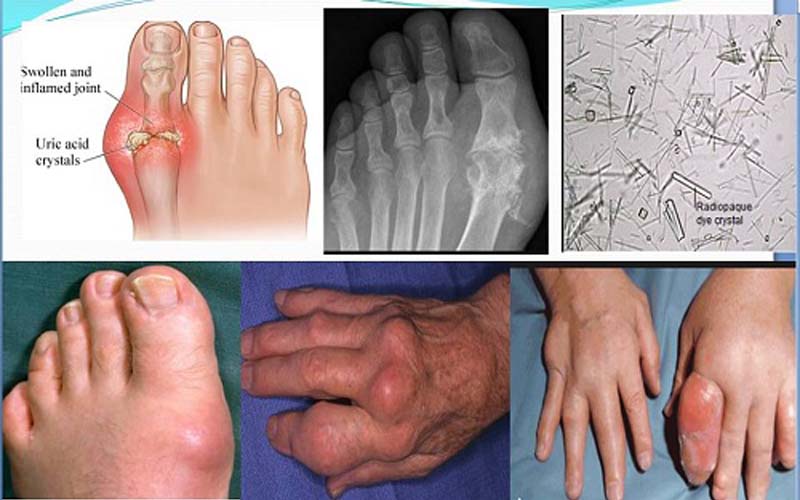

Tăng acid uric máu và sự chuyển hóa purin hình thành bệnh gout

Bệnh gout được xác định có nguyên nhân cốt lõi là do rối loạn chuyển hoá làm mất cân bằng giữa sự hình thành và đào thải acid uric, làm gia tăng đột ngột hàm lượng acid uric trong máu.